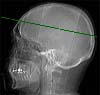

Radioanatomie TDM de l'encéphale avec injection

Artère péricalleuse

Scissure interhémisphèrique

Sinus sagittal supérieur

Faux du cerveau